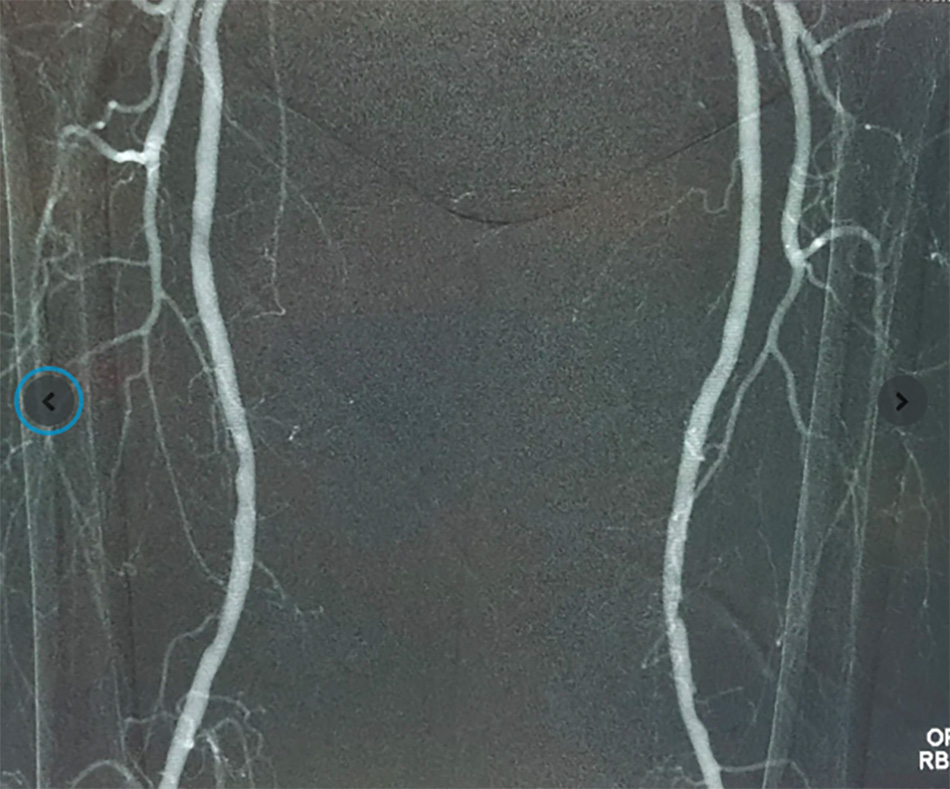

Kết quả siêu âm và chụp mạch tại FV cho thấy động mạch chậu phải bị tắc hoàn toàn đoạn dài, hẹp nặng động mạch chậu trái, động mạch chân phải bị tắc nghẽn hoàn toàn, động mạch chân trái tắc trên 90%. Máu từ tim gần như không xuống được hai chân. – lý do khiến ngón chân bị hoại tử và tình trạng đau nhức liên tục các ngón chân phải.

Ca phẫu thuật can thiệp mạch cho ông Đ. diễn ra trong phòng Cathlab với sự hỗ trợ của máy chụp mạch bằng khí CO₂ Angiodroid, hệ thống DSA Philips Allura Xper và các dụng cụ cần thiết. Mục tiêu của phẫu thuật là khai thông dòng máu đến được vết thương ở ngón chân, giúp cải thiện tình trạng lành thương cho bệnh nhân.

Sau hơn 3 tiếng cho ca phẫu thuật hybrid (kết hợp can thiệp nội mạch và phẫu thuật Bypass), kết quả cho thấy máu từ tim đã được dẫn đến cả hai chân người bệnh, giúp cải thiện tình trạng tưới máu.